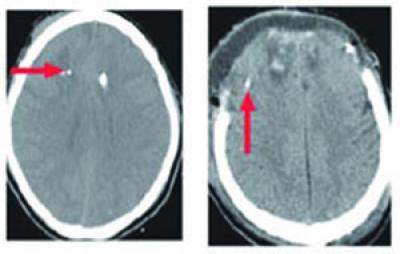

CT scans of the patients' brains guided catheter placement. In some patients the location of the injury was obvious and the catheter was placed nearby. In others, no injury was apparent on the scan and the catheters were simply placed in the same consistent location.